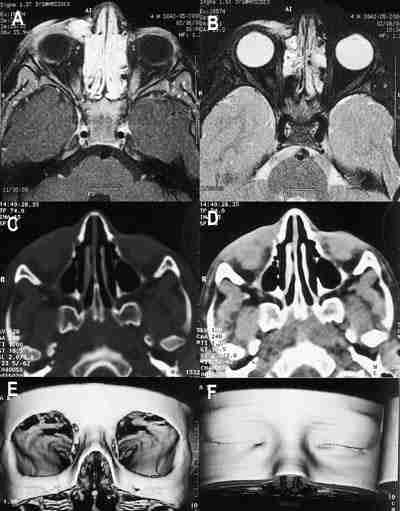

53-09.jpg (12346 bytes)

Figuras 9a, b, c y d. Hemangioma capilar. TC axial con adquisición helicoidal (a) con reconstrucción sagital (b). RM en secuencias sagital T1 y coronal T2 (c, d). Masa intra-extraconal hipercaptante con imágenes de vacío correspondientes a pequeños vasos en la RM (a).

53-10.jpg (19860 bytes)

Figuras 10a, b, c, d, e y f. Típica localización de linfangioma orbitario en la región cantomeatal. Secuencias potenciada en T1 con gadolínio (a) y en T2 (b) en las que no se observa afectación retrobulbar. TC axial en ventana ósea (c) y parenquimatosa (d) con reconstrucción tridimensional ósea (e) y de piel (f) muestran asimetría de párpado inferior y ausencia de afectación ósea.

53-11.jpg (13996 bytes)

Figuras 11a y b. Linfangioma: Secuencias coronal (a) y axial (b) potenciadas en T2 que muestran la lesión interconal multilobulada que brilla en T1 y T2.

53-12.jpg (15560 bytes)

Figuras 12a, b, c, d, e y f. Variz de la vena oftálmica superior. Secuencia axial potenciada en T1 pre y post administración de gadolínio (a, b). Corte axial con contraste yodado a nivel de la lesión (c) con reconstrucciones biplanares coronales (d) y sagitales (e). Angiografía venosa de la lesión (f). Se observa lesión en región teórica de la vena oftálmica superior que capta contraste marcadamente, y en la angiografía venosa (f) se observa el teñido correspondiente a la variz.